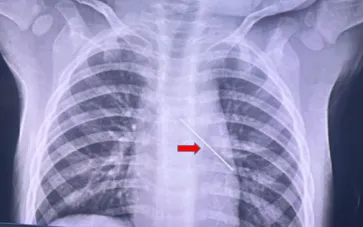

Tại bệnh viện địa phương, X-quang ngực ghi nhận dị vật kim loại trong đường thở. Sau sơ cứu ban đầu, bệnh nhi được chuyển khẩn cấp lên tuyến trên.

Khi nhập viện, bệnh nhi lừ đừ, SpO2 chỉ 88%, thở nhanh, co kéo ngực và có tiếng rít hai thì. Nghe phổi giảm thông khí bên trái. Các bác sĩ chẩn đoán dị vật phế quản giờ thứ 8 - tình trạng có nguy cơ đe dọa tính mạng.

Ekip Hô hấp - Tai Mũi Họng tiến hành nội soi phế quản cấp cứu. Hình ảnh cho thấy một kim cúc kim loại nằm ở phế quản gốc trái, đầu nhọn hướng lên sát carina. Dị vật ghim vào thành phế quản khiến việc gắp bằng kìm thông thường không thành công, nguy cơ xuyên thủng đường thở rất cao.